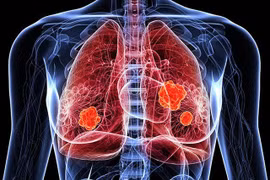

Ung thư phổi là một trong những dạng ung thư nguy hiểm nhất. Vì các dấu hiệu cảnh báo có xu hướng xuất hiện khi các tế bào ung thư đã nhân lên và lan sang các khu vực lân cận trong cơ thể.

Số bệnh nhân châu Á chiếm khoảng 60% tổng số ca ung thư phổi trên toàn thế giới, trong đó riêng Việt Nam có hơn 26.200 trường hợp được chẩn đoán mắc mới mỗi năm và gần 23.800 ca tử vong.